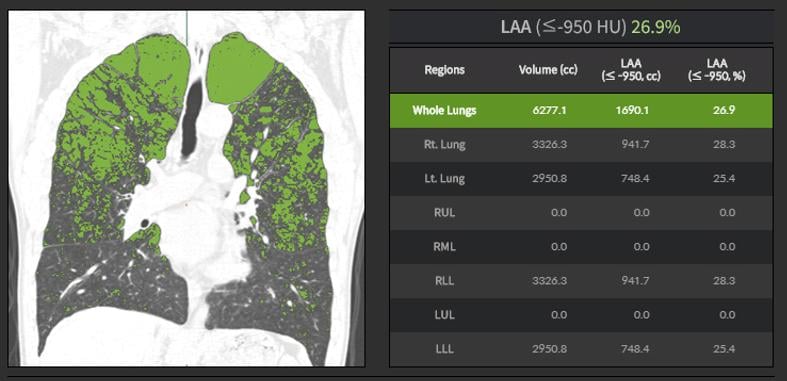

The PAIRR (Pulmonary Artificial Intelligence and Radiomics Research) Laboratory is a research unit of the Department of Radiology at UMass Memorial Medical Center and UMass Chan Medical School. Its mission is to develop, test, and implement innovative technology based on Artificial intelligence (AI) and Radiomics in the field of respiratory imaging.

The core research projects of the PAIRR Laboratory are based on accuracy and efficiency testing of novel AI and radiomics technologies. Additional research is focused on evaluating novel approaches to using these technologies, for example by combining or blending algorithms. Efficiency testing revolves around clinical algorithm implementation and the associated impact on work-flow and costs. Finally, a branch of research aims to develop and test mechanisms and metrics to quantify the “added-value” of novel technology to the clinical radiology workplace, and to analyze the increasing complexity of information generated by this technology.